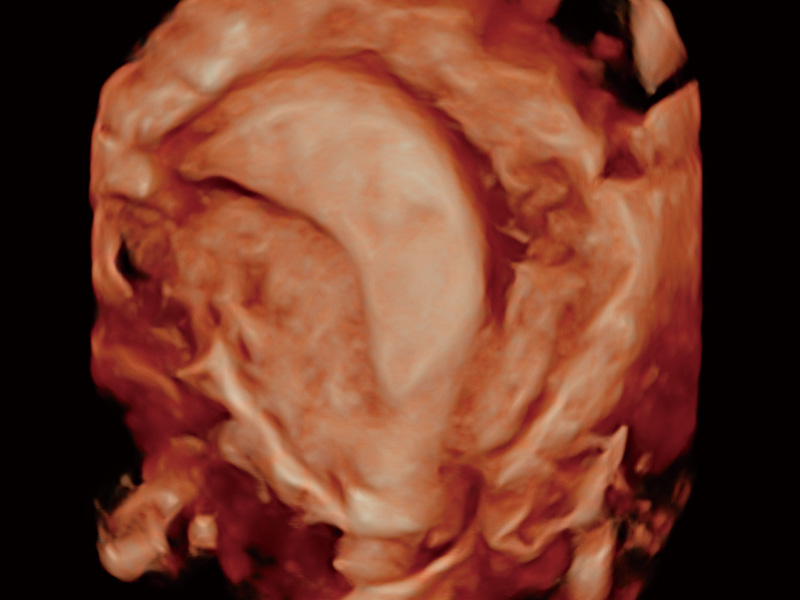

腔内三维成像技术获得显著提升,超大扇角在满足日常基础扫查的同时,支持卵泡自动测量及多种三维渲染模式,为您提供更多的诊断信息,尤其是在子宫畸形的诊断,内膜及肿瘤占位观测中起到了重要的作用。

单角子宫

子宫内膜息肉